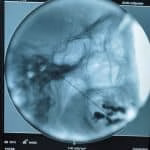

- Rizotomia percutânea lombar

- Implante de neuroestimulador medular